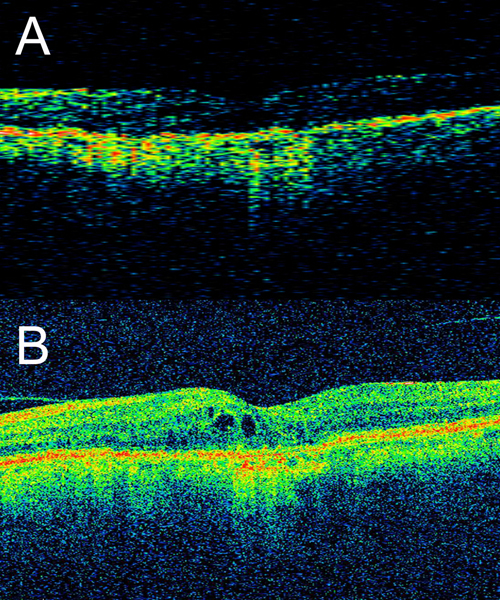

scans en modo B secuenciales permite la detección de movimiento (por ejemplo flujo sanguíneo). Tras la adquisición de imágenes de OCA es posible generar mapas tridimensionales del árbol vascular retinocoroideo, o imágenes del fondo de ojo en 2D con códigos de colores de la profundidad de los vasos (

Figura 6).

Figura 6. Angiografía de coherencia óptica (OCA). Combinando una plataforma OCT de swept source y un algoritmo de procesado de imágenes denominado SSADA (split-spectrum amplitude-decorrelation angiography) se puede evaluar el flujo a distintos niveles retinocoroideos sin la inyección de contraste, obteniendo imágenes de lo que se conoce como angiografía 3D. En el ejemplo de la imagen, publicado por el grupo del Dr. David Huang, se aprecia una neovascularización coroidea tipo 2 (clásica) perfectamente delimitada entre el epitelio pigmentario y la retina, con imágenes secuenciales a distintos planos, a nivel de la retina interna (D), la retina externa (E) y la coriocapilar-coroides interna (F). Además, es posible representar el nivel al que se encuentra la lesión en cortes convencionales (G y H), así como hacer reconstrucciones en 2D (J). (Fuente: Jia Y, Bailey ST, Wilson DJ, et al. Quantitative optical coherence tomography angiography of choroidal neovascularization in age-related macular degeneration. Ophthalmology. 2014;121(7):1435-44).